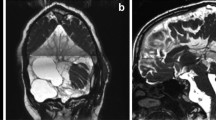

This is an autosomal recessive inborn error of metabolism [75]. A deficiency in glutaryl-CoA dehydrogenase enzyme results in motor symptoms such as dystonia and psychomotor delay due to an inability to catabolize lysine, hydroxylysine, and tryptophan [75]. Macrocephaly, dystonia, and the presence of bilateral temporal ACs are considered diagnostic of GA-1 [72, 75, 115]. However, there is no clear indication of whether the ACs are directly linked to the syndrome as treating the cysts did not relieve the symptoms [75]. The severity of the symptoms has been found to be directly linked to the degree of enlargement of the fissures in the bilateral frontotemporal region around the Sylvian fissures [3, 57, 72]. There can be variation in the presentation of clinical symptoms both between and within families [26].

Hald et al. posed an explanation as to how ACs might arise in patients with GA-1. The rapid frontotemporal atrophy would lead to changes in CSF dynamics and cause fluid accumulation [45]. If these changes took place during the folding of the neural tube, then it can result in anomalous splitting of the arachnoid layers resulting in true ACs [45]. Alabedeen et al. found that in GA-1 the location of the ACs aligns with the areas of the brain that are predisposed to atrophy (i.e., the frontotemporal region) [57]. This paper argued that the arachnoid membrane might split due to loss of brain tissue in the surrounding areas and not due to the enzyme imbalances brought about by GA-1 [57]. Other papers in the literature support this hypothesis [3, 72]. An alternative theory is that the atrophy and chronic subdural effusion might be caused by the 3-OHGA affecting endothelial structures in the brain during development and resulting in vascular dysfunction [26].

While the paper by Martinez-Lage et al. [45] discusses how ACs are a part of the GA-1 syndrome, Serarslan et al. and other papers explore how bitemporal ACs and macrocephaly can occur in the absence of GA-1 [57, 118]. GA-1 is diagnosed by the detection of a high concentration of glutaric acid in the urine and a low plasma creatinine level [118]. There were patients present with bilateral ACs and no diagnosis of GA-1 [72, 118]. Thus, ACs can occur for many reasons, but they are commonly associated with GA-1. If they are found either on scans, especially alongside macrocephaly and dystonia, doctors should consider GA-1 as a differential diagnosis [45, 72, 118]. This is extremely important because even simple surgical procedures can be dangerous in children with GA-1 [72]. Surgery would induce a catabolic state in the patient and result in worsening of the metabolic disease.